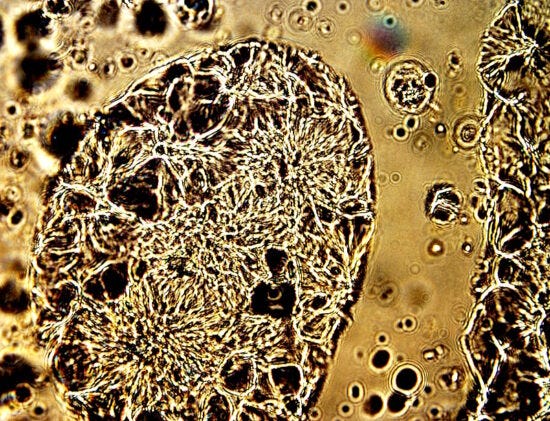

We start the discovery with a case study of skin affliction as a consequence of synthetic biology (CDB), a topic extensively developed within this site. Identification is simple and repetitious with the use of microscopy alone, and examples are given in the recent paper, “Cruel and Unusual Suffering”, Aug 2025. Please refer to that paper for an additional reference point.

CDB (Synthetic Biology) in Afflicted Skin

Original Magnification 3200x